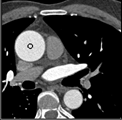

Samples for ascending aorta detection (black circle):

Cluster of candidate points in the ascending aorta.